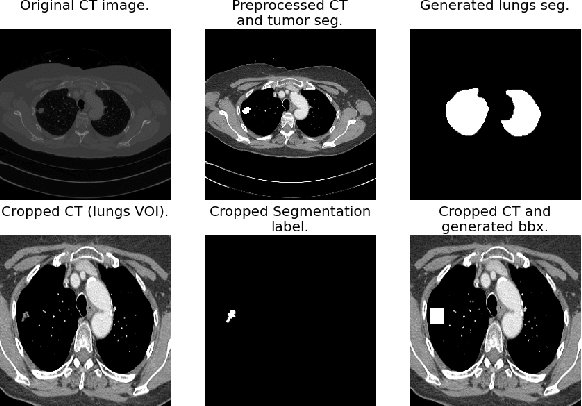

Lung cancer is a leading cause of death worldwide. Early-stage detection of lung cancer is essential for a more favorable prognosis. Radiogenomics is an emerging discipline that combines medical imaging and genomics features for modeling patient outcomes non-invasively. This study presents a radiogenomics pipeline that has: 1) a novel mixed architecture (RA-Seg) to segment lung cancer through attention and recurrent blocks; and 2) deep feature classifiers to distinguish Epidermal Growth Factor Receptor (EGFR) mutation status. We evaluate the proposed algorithm on multiple public datasets to assess its generalizability and robustness. We demonstrate how the proposed segmentation and classification methods outperform existing baseline and SOTA approaches (73.54 Dice and 93 F1 scores).